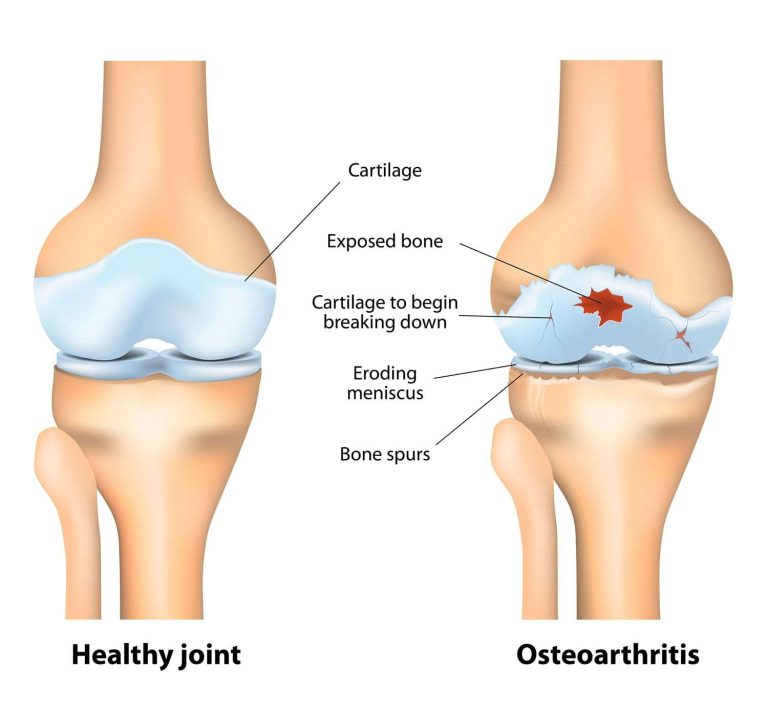

Orthopedic issues are more common than you think. From arthritis and ligament tears to fractures and sports injuries, these problems affect people of all ages. Common signs include chronic pain, stiffness, swelling, reduced mobility, or frequent injuries. Ignoring them can lead to long-term damage and loss of functionality. That’s why seeking timely care from a bone specialist in Bangalore, like Dr. G.K is crucial.

5. Arthritis Treatment-

Arthritis affects millions and can seriously impact quality of life. We offer medication, physiotherapy, and surgical solutions like joint replacement to help patients regain mobility.